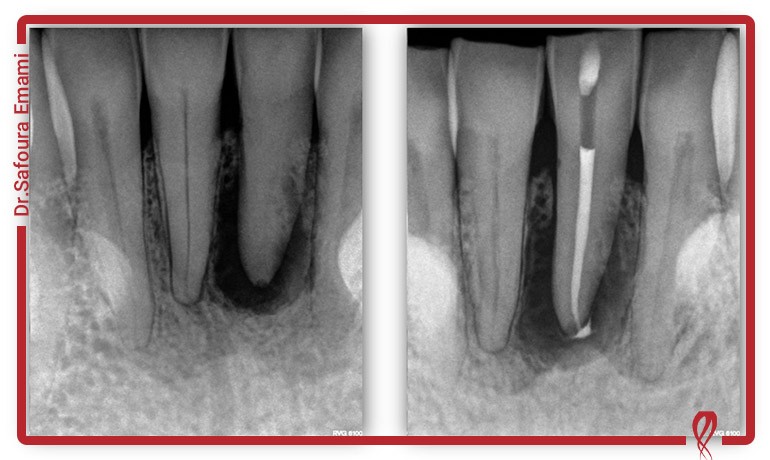

- رادیوگرافیهای دیجیتال باکیفیت: ررادیوگرافی دندان اولین سرنخها را در مورد وجود و شدت کلسیفیکاسیون ارائه میدهند.

- تصویربرداری سه بعدی (CBCT): این تکنولوژی یک انقلاب در دندانپزشکی است. تصویربرداری CBCT یک نمای سه بعدی و دقیق از ساختار ریشه، تعداد کانالها و محل دقیق کلسیفیکاسیون در اختیار دندانپزشک قرار میدهد. این نقشه سه بعدی، ریسک خطا را به حداقل میرساند.